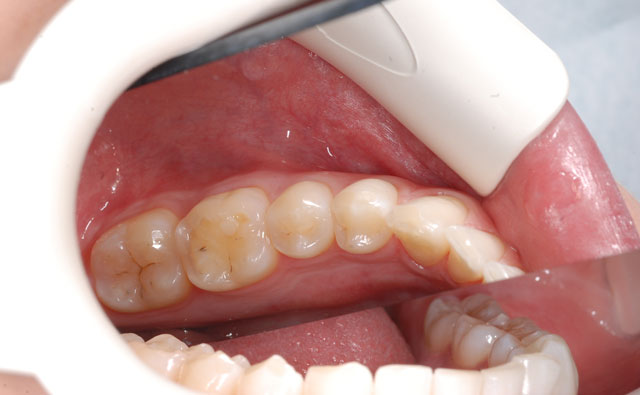

3.口腔内写真

高画質カメラで色々な角度から口腔内の写真を撮ります(10枚以上)。その写真を患者さんと一緒に見る事によって、患者さんがより理解しやすくなるのは勿論、記録に残し毎年比べる事で、歯茎が下がっていないか、歯並びに変化がないか、なども知ることができます。パソコン画面で拡大して見る事もでき、口腔癌を早期発見できた、という例もあります。